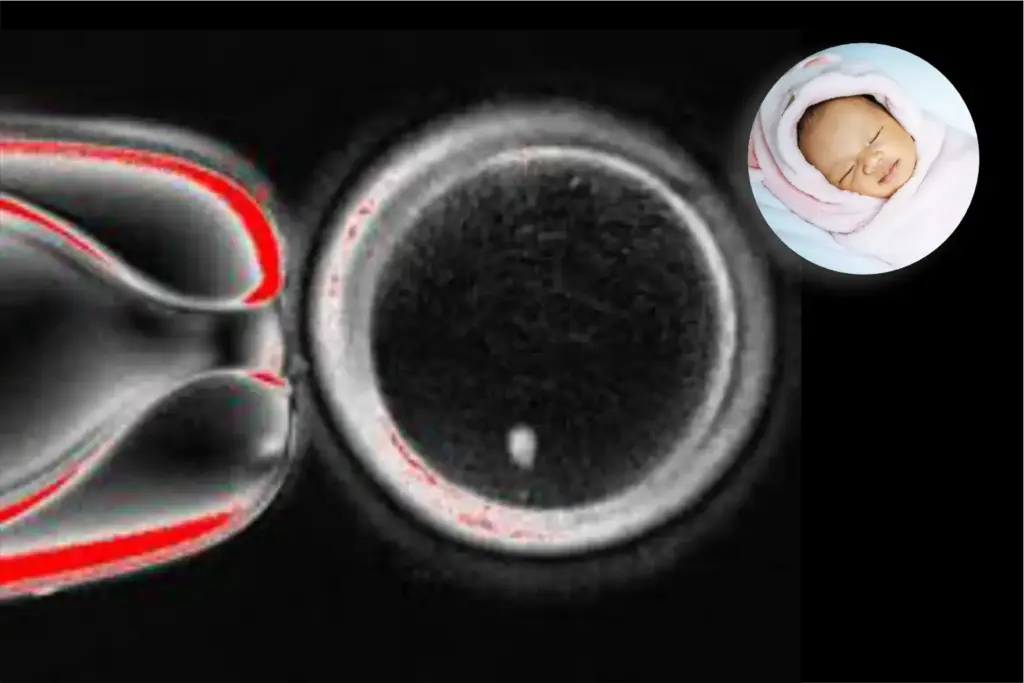

In the experiment, researchers removed the nucleus from a donated human egg and inserted the nucleus of a skin cell, which naturally contains two chromosome sets. They then induced the reconstructed egg to shed extra chromosomes (eggs and sperm, each should carry just one set) before injecting donor sperm and initiating development. About 9% of the constructs progressed to six days in culture, reaching the blastocyst stage, at which point the work was halted.